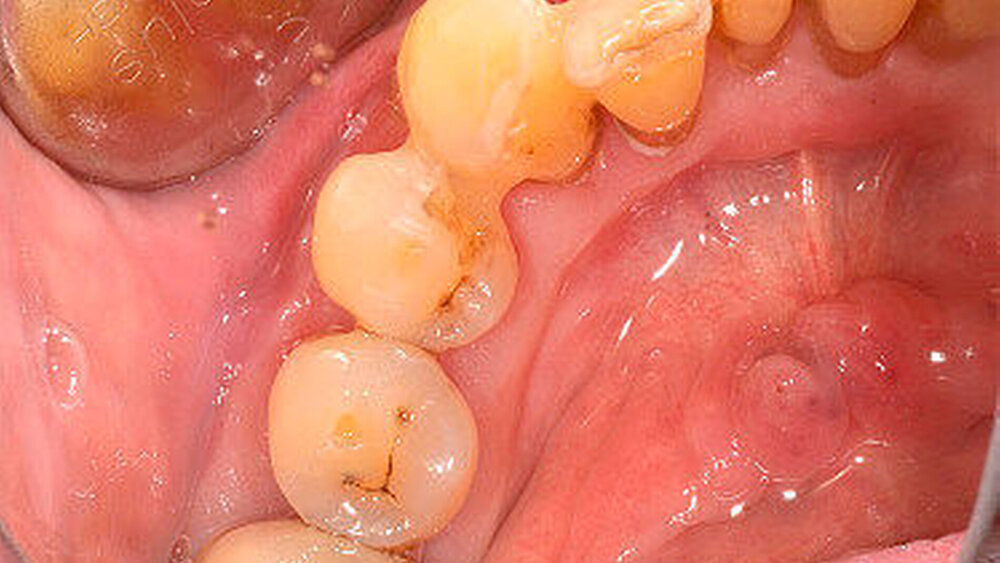

Nach 48 Stunden i.v.-Antibiose und intensiver Hygienisierung (Abbildung 3) erfolgte die Abtragung der Gingivanekrose unter laufender Dabigatran-Medikation. Die sich von Zahn 32 bis 35 vestibulär und interdental erstreckende Nekrose wurde schonend entfernt (Abbildung 4). Eine Mitbeteiligung des Alveolarknochens war nicht erkennbar. Im Anschluss erfolgte eine chemische Dekontamination der Wunde mit Betaisodona-Lösung sowie der primäre Wundverschluss mittels modifiziertem koronalen Verschiebelappen (Nahtmaterial: Resolon 4.0, Resorba Medical GmbH). Die Zähne 32 bis 34 wurden aufgrund ihrer geringgradigen Lockerung belassen und mittels Säure-Ätz-Technik primär durch Schienung stabilisiert. Abschließend erfolgte die Abdeckung des OP-Situs mit einer Verbandsplatte, in welche im vestibulären Bereich eine Aussparung eingearbeitet wurde (Abbildung 5).

In diese Aussparung wurde ein mit Gentamycinsalbe getränkter Gazestreifen eingelegt. Die histopathologische Begutachtung des entfernten Materials ergab eine floride akut-nekrotisierende und chronische Entzündung, die nach Art und Umfang gut mit einer akut nekrotisierenden ulzerierenden Gingivitis (ANUG/NUG) vereinbar ist.